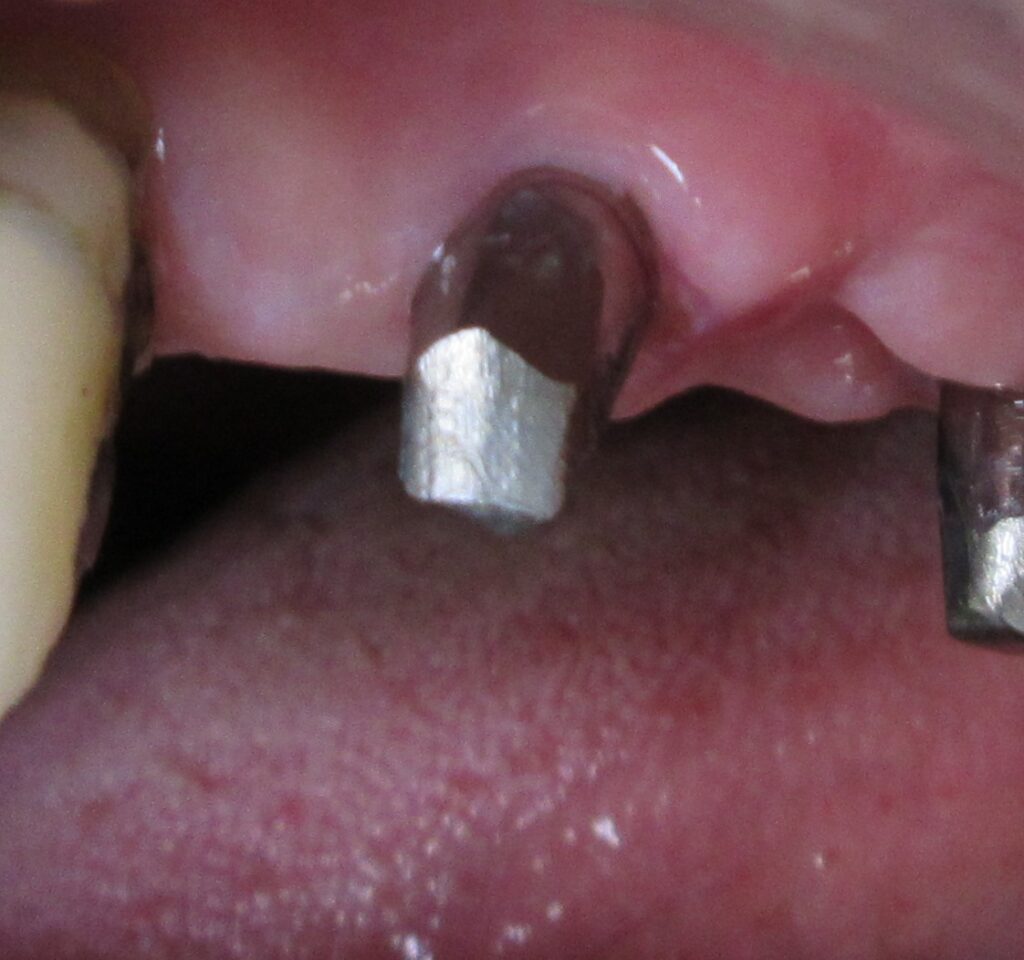

開けた穴に、専用道具を使ってネジを締めるように長さ2センチ程のインプラントを骨に埋め込んでいきます。

しっかりとインプラント埋め込まれた後は、動揺がないか、噛んだ時に当たらないかなどを確認して、最後にパノラマ写真を撮影して今回のオペは終了となりました。